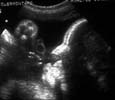

Oropharynx : En arrière de la langue en coupe transversale, petite image ronde ou ovalaire. Parfois virtuelle en fonction des mouvements de déglutition. Déjà bien visible à 20 SA